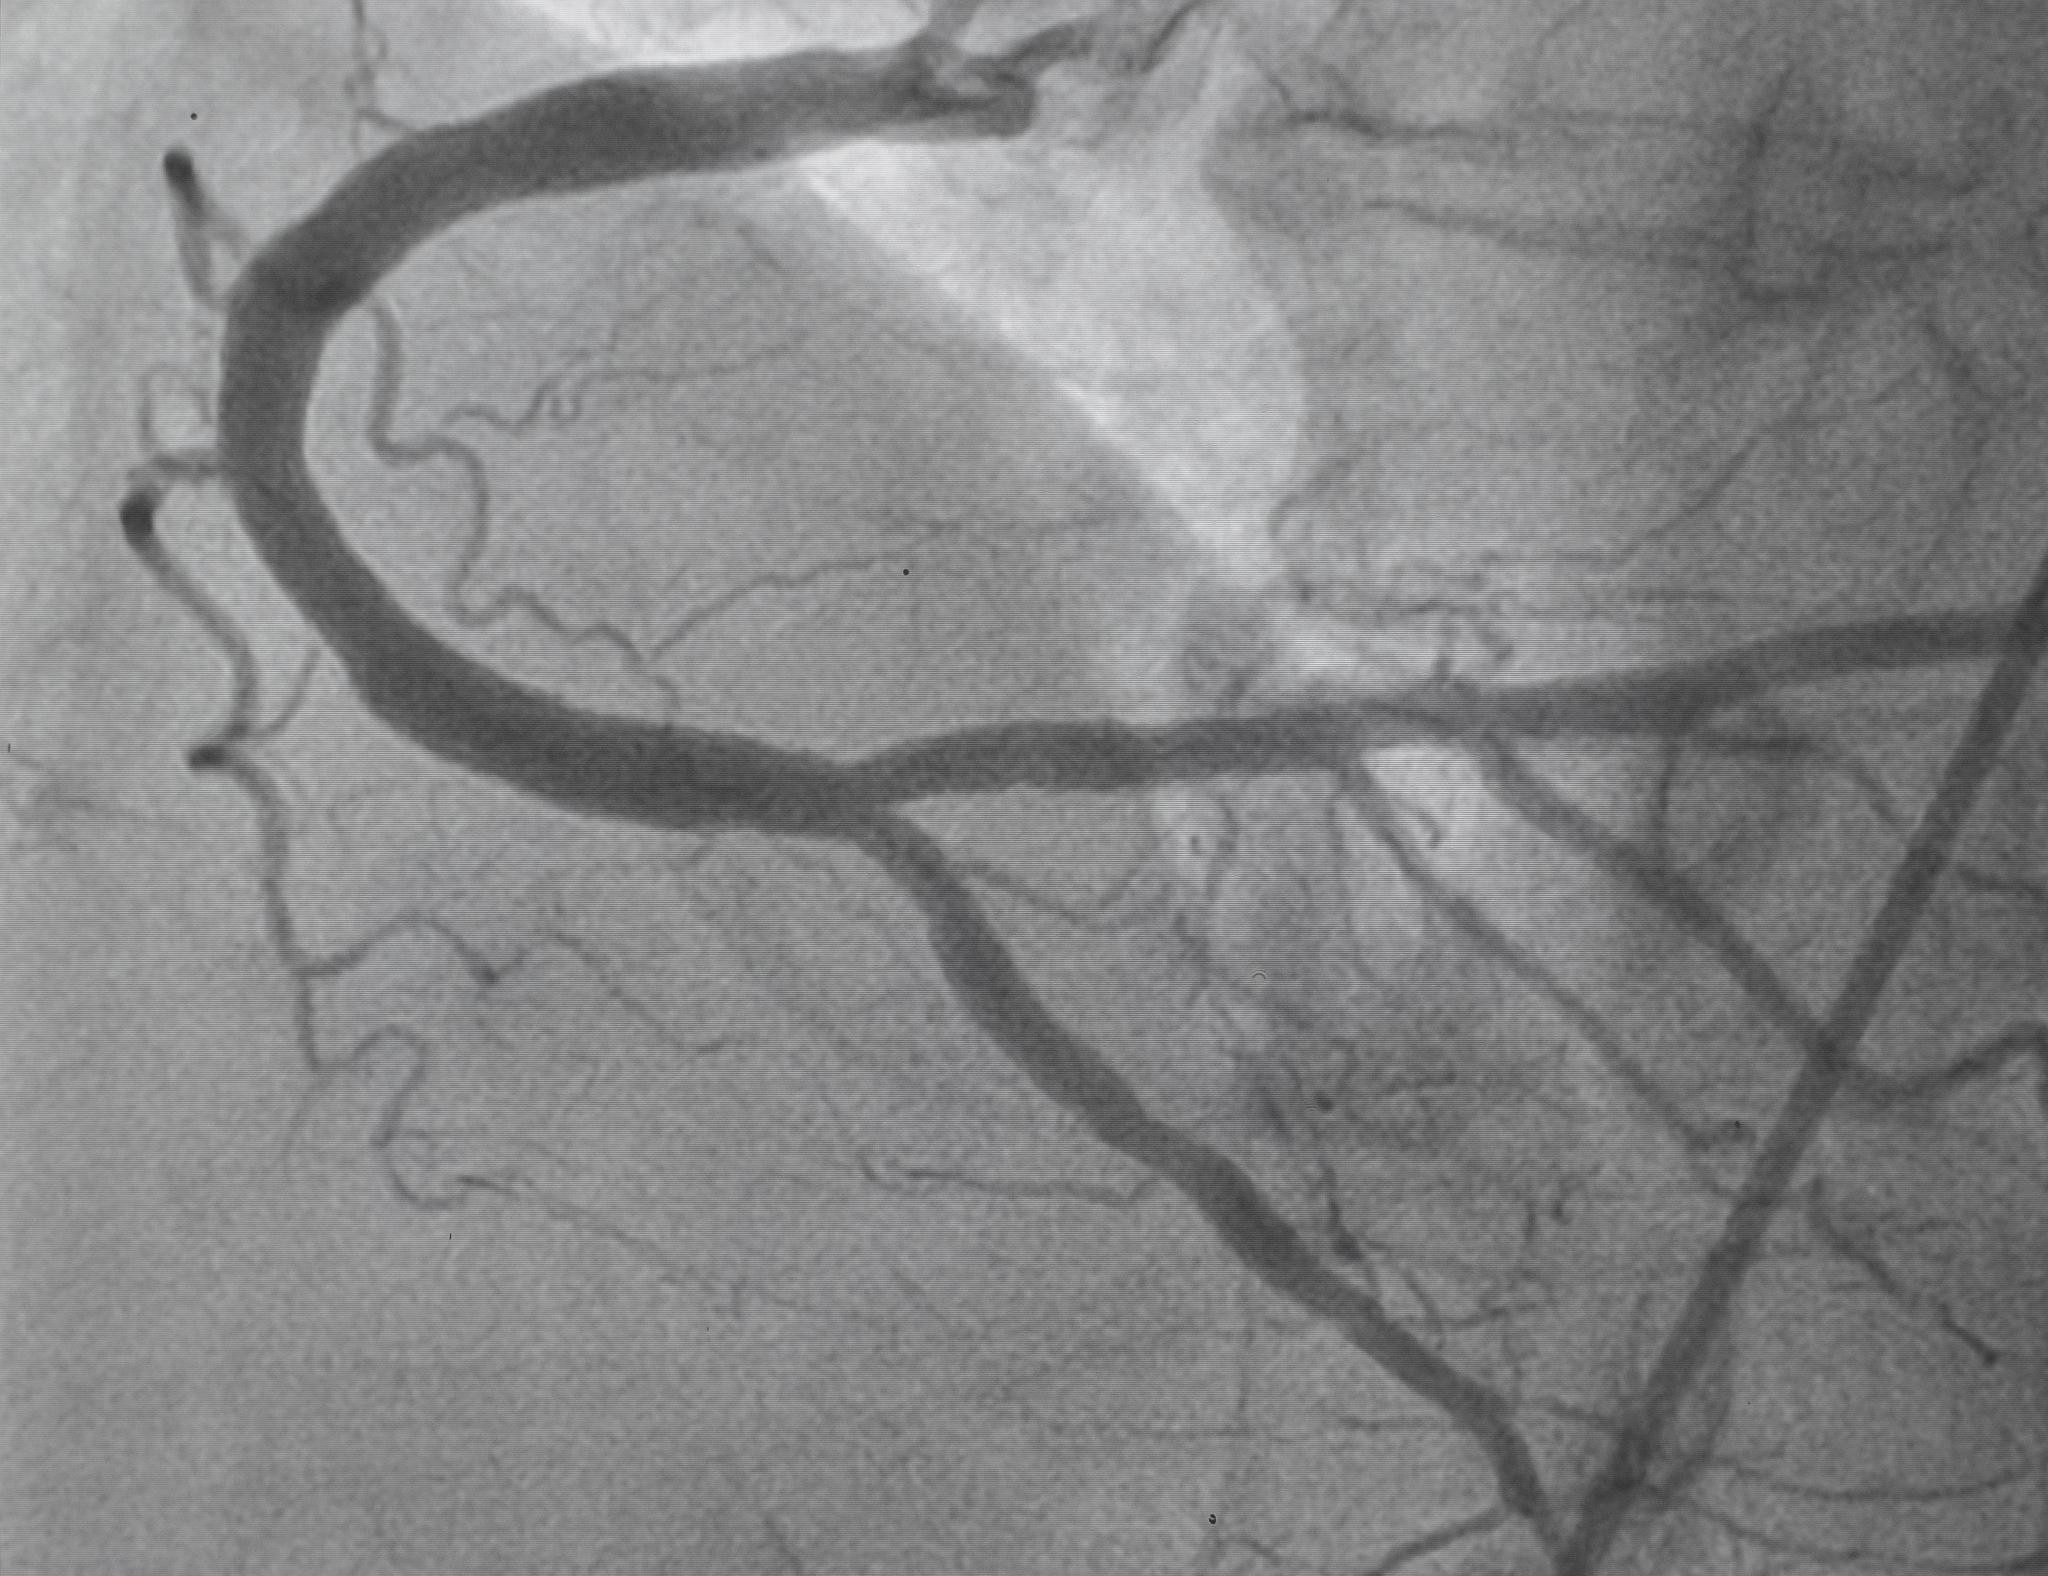

Early and timely diagnosis of vulnerable plaques in the carotid artery that may rupture and cause embolism is crucial, as the presence of free-floating thrombi can lead to more severe strokes and has significant implications for reducing stroke-related morbidity and mortality. Carotid ultrasound imaging is a recommended diagnostic method, due to its simple and convenient operation, real-time monitoring, non-radiation exposure, and bedside examination.